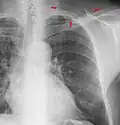

In the average person, the diaphragm should be intersected by the 5th to 7th anterior ribs at the mid-clavicular line, and 9 to 10 posterior ribs should be viewable on a normal PA inspiratory film. An increase in the number of viewable ribs implies hyperinflation, as can occur, for example, with obstructive lung disease or foreign body aspiration. A decrease implies hypoventilation, as can occur with restrictive lung disease, pleural effusions or atelectasis. Underexpansion can also cause interstitial markings due to parenchymal crowding, which can mimic the appearance of interstitial lung disease. Enlargement of the right descending pulmonary artery can indirectly reflect changes of pulmonary hypertension, with a size greater than 16 mm abnormal in men and 15 mm in women.[6]

Appropriate penetration of the film can be assessed by faint visualization of the thoracic spines and lung markings behind the heart. The right diaphragm is usually higher than the left, with the liver being situated beneath it in the abdomen. The minor fissure can sometimes be seen on the right as a thin horizontal line at the level of the fifth or sixth rib. Splaying of the carina can also suggest a tumor or process in the middle mediastinum or enlargement of the left atrium, with a normal angle of approximately 60 degrees. The right paratracheal stripe is also important to assess, as it can reflect a process in the posterior mediastinum, in particular the spine or paraspinal soft tissues; normally it should measure 3 mm or less. The left paratracheal stripe is more variable and only seen in 25% of normal patients on posteroanterior views.[7]

Localization of lesions or inflammatory and infectious processes can be difficult to discern on chest radiograph, but can be inferred by silhouetting and the hilum overlay sign with adjacent structures. If either hemidiaphragm is blurred, for example, this suggests the lesion to be from the corresponding lower lobe. If the right heart border is blurred, than the pathology is likely in the right middle lobe, though a cavum deformity can also blur the right heard border due to indentation of the adjacent sternum. If the left heart border is blurred, this implies a process at the lingula.[8]